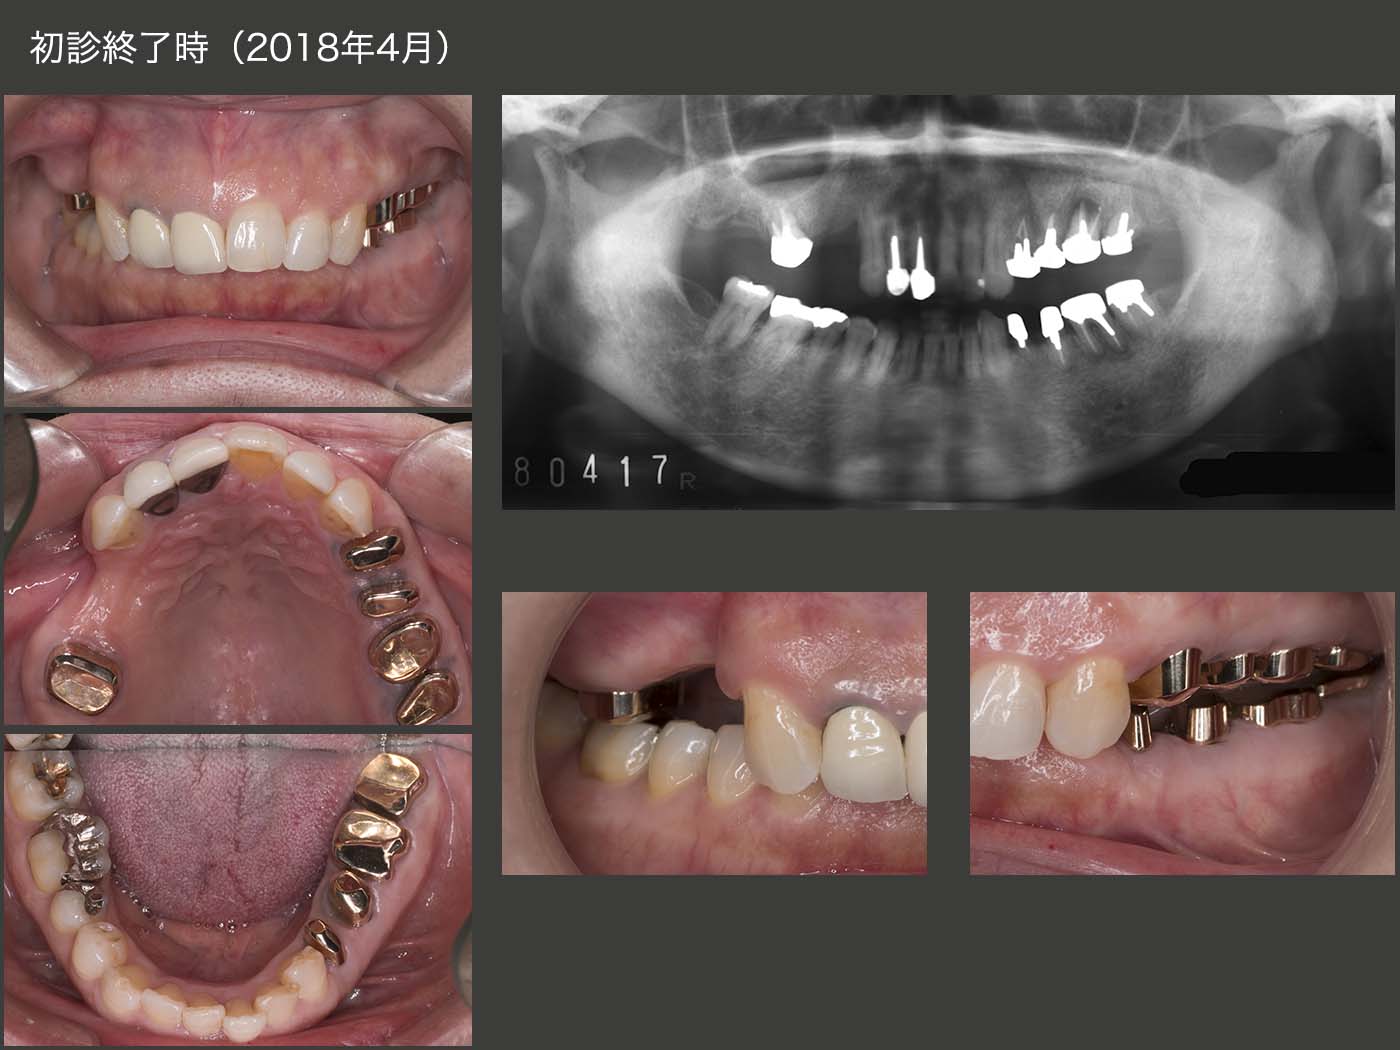

最終的には,まず感染根管治療を施し,歯冠長延長術を行って歯肉縁上歯質を確保し,歯根が短くなった分は連結固定で補うという設計方針を立案した.また1次固定では,歯の清掃がしにくいこと,将来の変化に対応しにくいことから,2次固定を採用することにした.

2018年4月,初診終了時の状態.右上については,即時義歯のままでも構わないが,咬合高径がない分,支台装置をくるむレジン量が少ないことが危惧された.そこで,義歯の破折を予防するために,さらに強固な義歯に作り換えた.(咀嚼の中心は左側のため,右側の義歯の破折は生じにくい.少々オーバートリートメントの感は拭えない.)

義歯を装着した状態.上下左側の個々の歯は当初条件が悪かったが,連結固定したことで咬合・咀嚼力に対応でき,また左側の咬合支持を強固に得られたことは,今後の経過によい影響を及ぼすであろうと期待している.ただ,左側の偏咀嚼および咬み過ぎによる歯根破折の問題もあるので,意識して右側でも咀嚼して貰うこと,また,あまり硬いものを左側で咬まないようにお願いしている.